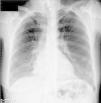

Further diagnostic tests revealed normal myocardial necrosis markers, elevated BNP, rhabdomyolysis, severe hypocalcemia and type 1 respiratory failure (Table 2). The electrocardiogram (ECG) (Figure 1) showed long QT interval (QTc 0.53 s) and T-wave inversion in V2–V4 and DI. The posteroanterior chest X-ray (Figure 2) revealed interstitial infiltration in the lower third of both lung fields, suggestive of edema.